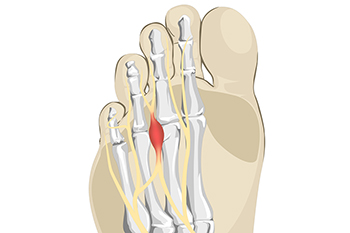

Painful Symptoms Are Often Associated With Morton’s Neuroma

[Morton's neuroma](https://medicalwaveus.com/mortons-neuroma-treatment-causes-symptoms/) is a foot condition that affects the nerves between the metatarsal bones in the foot. These are long…